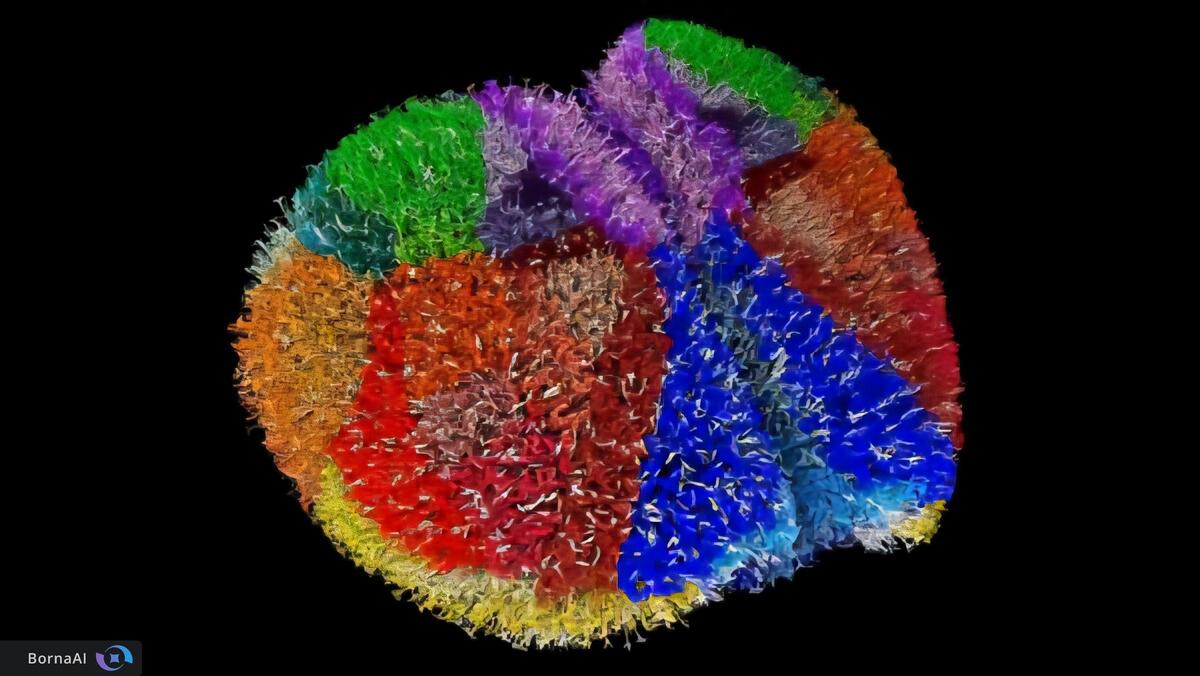

با استفاده از ComSLI پژوهشگران موفق به تصویربرداری از برشهای کامل مغز انسان شدند و جزئیات دقیقی از ساختارهای مختلف مغزی را مشاهده کردند. آنها همچنین تغییرات الیافی ناشی از بیماریهایی ماننداماس، لکوآنکفالوپاتی و آلزایمر را بررسی کردند.

در ناحیه هیپوکامپ که نقش کلیدی در حافظه دارد، بافت مغز فرد مبتلا به آلزایمر کاهش چشمگیر ارتباطات الیافی را نشان داد. مسیرهای حیاتی انتقال اطلاعات حافظه بهویژه مسیر پرفورانت تقریبا از بین رفته بودند؛ در حالی که هیپوکامپ سالم شبکهای متراکم و پیوسته از الیاف را نمایش میداد. این تصاویر امکان مشاهده مستقیم تخریب مدارهای حافظه را فراهم میکند. جالب آنکه تیم پژوهشی حتی یک نمونه مغزی مربوط به سال ۱۹۰۴ را نیز بررسی کرد و با وجود قدمت بیش از یک قرن مسیرهای پیچیده الیافی در آن قابل شناسایی بود.